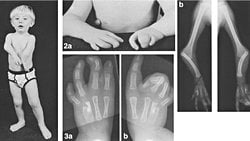

Baller-Gerold sendromu, belirli kafatası kemiklerinin erken kaynaşması (kraniyosinostoz) ve kol ve ellerdeki kemik anormallikleri ile karakterize nadir bir durumdur.

Baller-Gerold sendromlu kişilerde, çoğunlukla koronal sütür, yani başın üzerinden kulaktan kulağa geçen büyüme çizgisi boyunca, erken kaynaşmış kafatası kemikleri vardır. Kafatasının diğer dikişleri de kaynaşmış olabilir. Bu değişiklikler anormal şekilli bir kafa, belirgin bir alın ve sığ göz yuvalarına sahip şişkin gözler (oküler proptozis) ile sonuçlanır. Diğer ayırt edici yüz özellikleri arasında geniş aralıklı gözler (hipertelorizm), küçük bir ağız ve eyer şeklinde veya az gelişmiş bir burun sayılabilir.

Ellerdeki kemik anormallikleri, eksik parmakları (oligodaktili) ve hatalı biçimlendirilmiş veya eksik parmakları içerir. Önkolda kemiklerin kısmen veya tamamen yokluğu da yaygındır. Birlikte, bu el ve kol anormalliklerine radyal ışın malformasyonları denir.

Baller-Gerold sendromlu kişilerde bebeklik döneminde başlayan yavaş büyüme, küçük boy ve bozuk veya eksik diz kapakları (patella) gibi çeşitli ek belirti ve semptomlar olabilir. Doğumdan birkaç ay sonra genellikle kollarda ve bacaklarda deri döküntüsü görülür. Bu kızarıklık zamanla yayılır, cilt renginde düzensiz değişikliklere, ciltte incelme alanlarına (atrofi) ve derinin hemen altındaki küçük kan damarı kümelerine (telanjiektazlar) neden olur. Bu kronik cilt sorunları topluca poikiloderma olarak bilinir.

- Kraniyofasiyal Bulgular: Koronal kraniyosinostoz, klinik olarak oküler proptozis ve belirgin alın ile kafatasının anormal şekli (brakisefali) olarak kendini gösterir ve kafatası röntgeni veya tercihen 3D-CT rekonstrüksiyonu ile doğrulanır. Koronal sütürler kaynaştığında yörünge öne doğru çekilir. Koronal dikişler önden görünümde ayırt edilemez ve aynısı lambdoidal dikişler için de geçerlidir,

- İskelet Anomalileri: Radyal ışın defekti, başparmağın aplazisi/hipoplazisi veya yarıçapın aplazisi/hipoplazisi olarak kendini gösterir (Küçük radyal ışın malformasyonlarının doğrulanması için radyograflar gerekli olabilir),